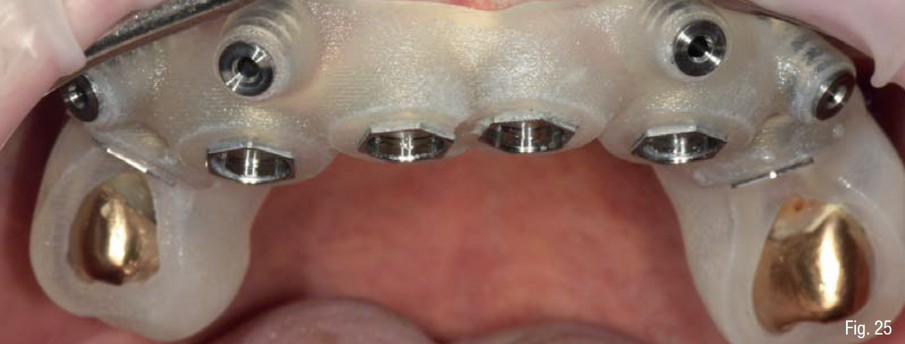

Durante la fase di chirurgia implantare, è stata inizialmente fissata la dima chirurgica sfruttando l’appoggio dento-mucoso; successivamente, è stata eseguita un’incisione lineare crestale e si è proceduto al sollevamento di un lembo vestibolare a tutto spessore e alla rimozione delle mini-viti e della griglia, che essendo osteointegrata in diversi punti è stata rimossa in diversi frammenti. La percentuale di rigenerazione, ovvero il rapporto tra il volume osseo rigenerato e il volume osseo pianificato, è stato calcolato essere del 96% (Figg. 25-29). La dima chirurgica è stata riposizionata e fissata nuovamente mediante i pin di fissaggio precedente preparati, non avendo più il supporto mucoso. Usando una tecnica di sotto-preparazione, sono stati realizzati i siti implantari e sono poi stati inseriti i 6 impianti programmati: 4 impianti dritti con dimensione 10 x 3.7 mm e 2 impianti angolati a 25° con dimensione 12 x 3.7 mm, al fine di evitare il seno mascellare (BTK implant Isy+, Biotec Srl, Dueville, Vicenza, Italy) (Fig. 30).